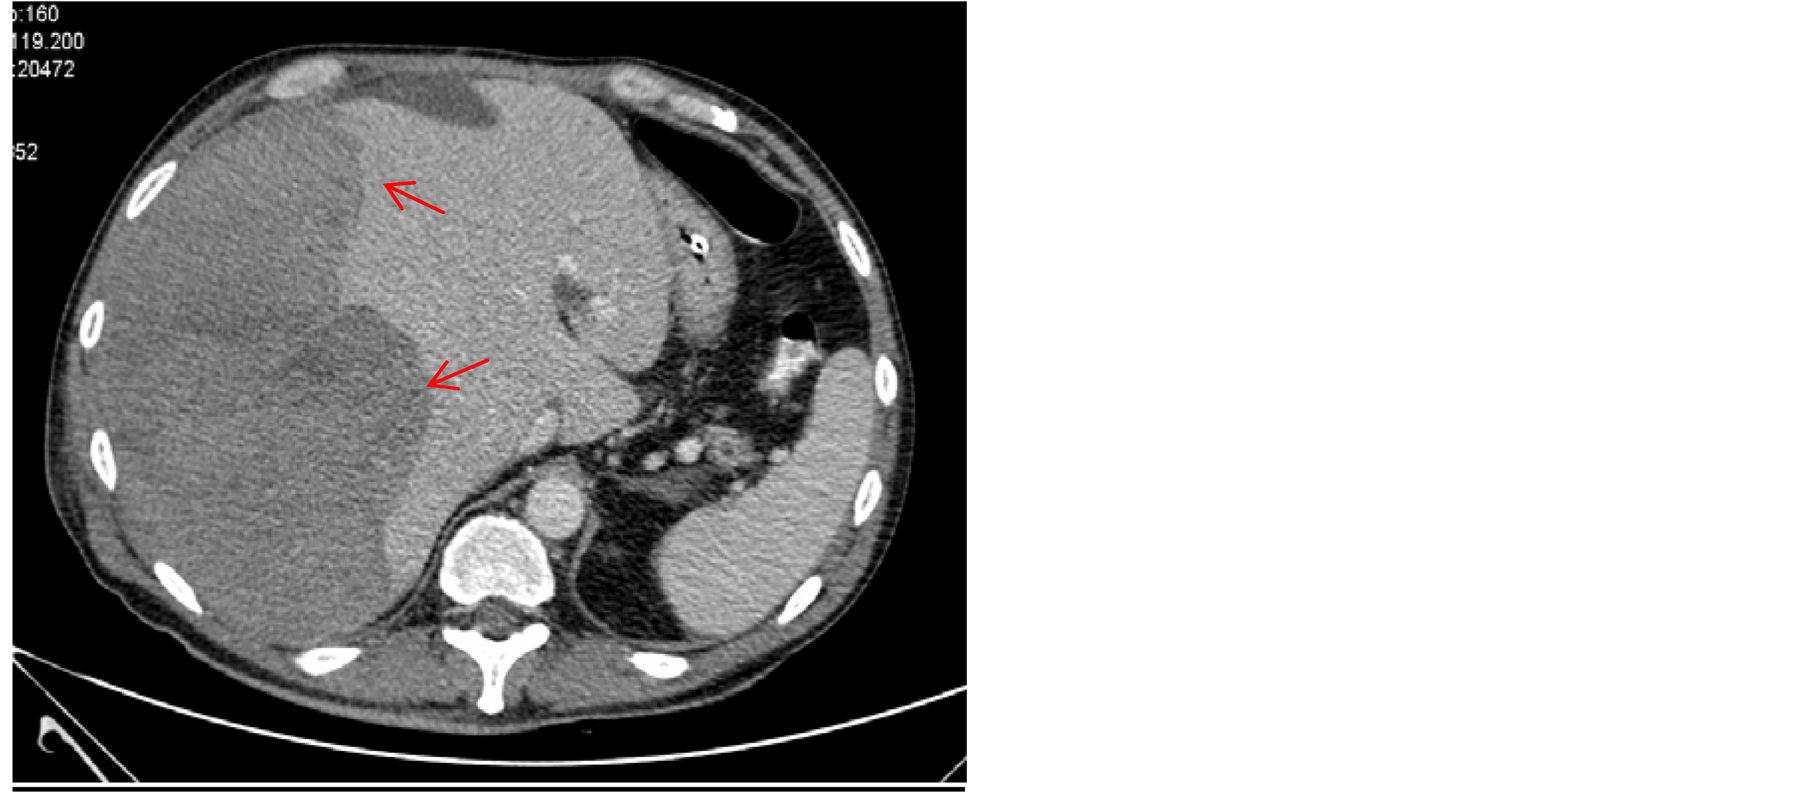

Over the following six hours, the patient developed right-sided upper abdominal pain with no clear sign of abdominal tenderness. The hemoglobin level declined from 14 g/dL to 8 g/dL. An urgent abdominal computed tomography (CT) scan revealed subcapsular hematoma surrounding the whole right hepatic lobe, with dimensions of 19 × 17.8 × 6.9 cm (Figure 2). Due to new anemization, despite blood transfusions, and hemodynamic

Figure 2. Abdominal CT scan reveals hepatic subcapsular hematoma with dimensions of 19 × 17.8 × 6.9 cm (red arrows).